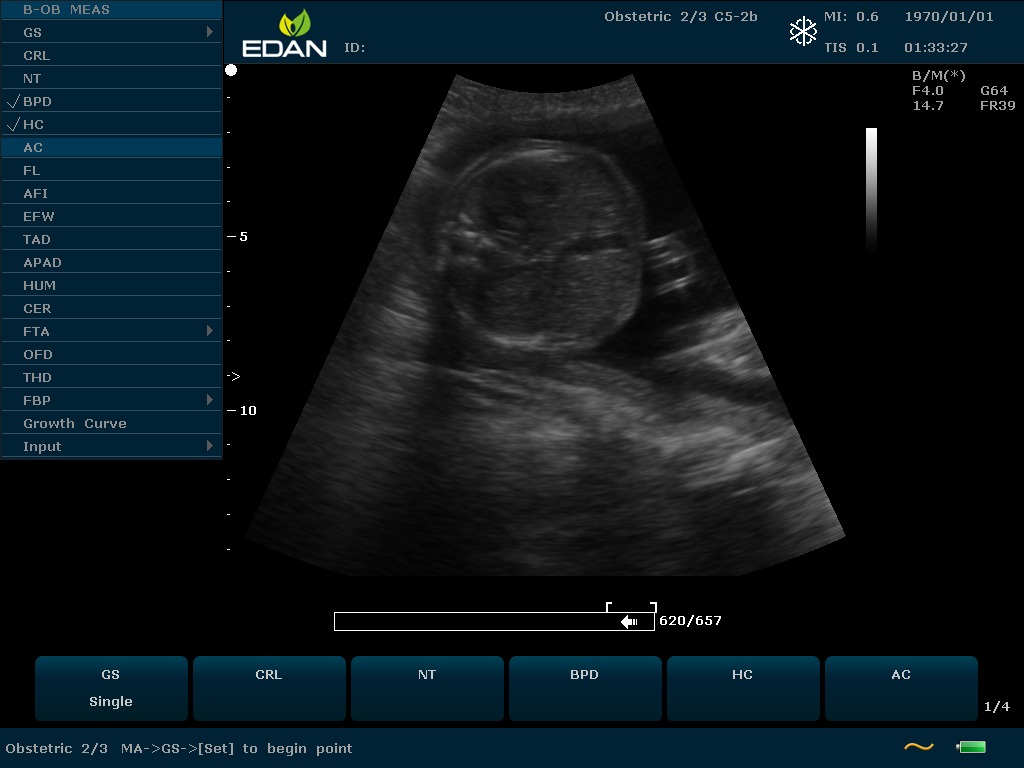

Особенность U60 Edan — расширенное применение. Ультразвуковой аппарат рекомендован для абдоминальных исследований, гинекологии и акушерства, кардиологии, педиатрии, урологии, изучения малых органов, сосудов. Для U60 Edan используются конвексные, линейные, фазированные и внутриполостные датчики.

Передовые технологии позволяют повысить качество визуализации в несколько раз. УЗИ-аппарат U60 Edan отличается возможностью быстрой настройки визуализации. Специальные функции позволяют моментально отображать данные за счет быстрой оптимизации параметров. Режимы визуализации: B-mode, M-mode, Color Doppler, Power Doppler Imaging, Pulsed Wave Doppler, Continuous Doppler.

• Пакет программ измерений и вычислений